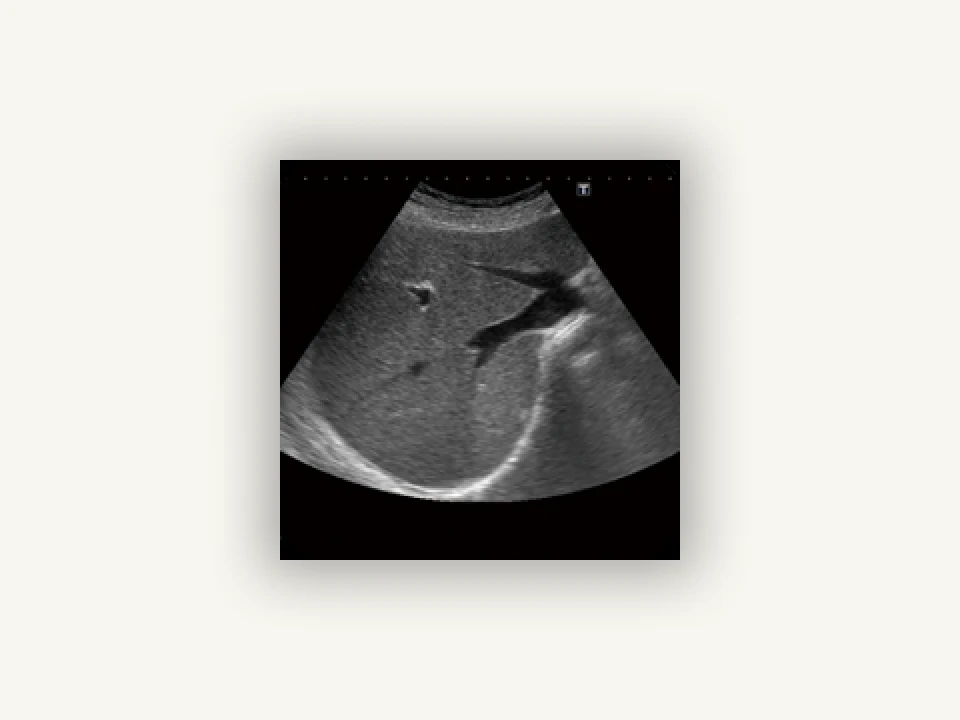

腹部エコー

「腹部エコー」とは?

腹部に超音波を当て、肝臓や胆のう、腎臓などの内臓を調べる検査です。内臓に腫瘍やポリープ、炎症、結石などがないか分かります。

胆石症、肝腫瘍、腎のう胞など腹部の内蔵の様子が分かります。

ベッドに仰向けになり、エコーを腹部に当てます。放射線被ばくの心配もなく、痛みもありません。検査は15分ほどで終わり、細かな説明をおこないます。